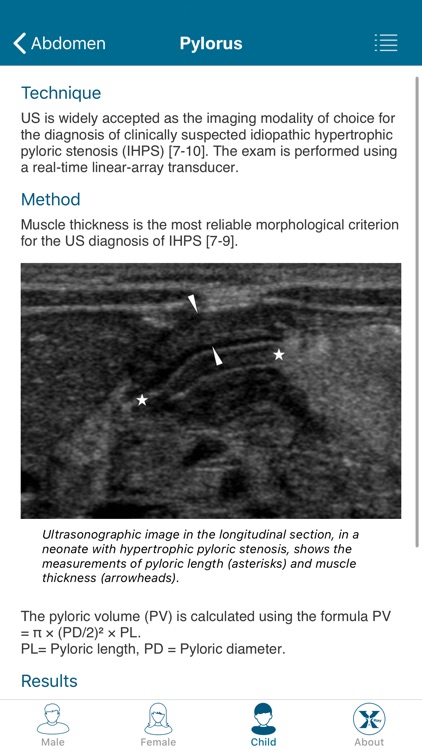

Created by radiologists for all those who practice medical imaging, this application constitutes an atlas of the main measurements in radiology and their normal values based on the most cited literature. It illustrates easy and reproducible methods using different imaging methods.

Created by radiologists for all those who practice medical imaging, this application constitutes an atlas of the main measurements in radiology and their normal values based on the most cited literature. It illustrates easy and reproducible methods using different imaging methods.

The application covers multiple imaging modalities: radiography, ultrasound, CT and MRI. The modules are divided into six sub-specialties: osteoarticular, cervical region, thorax, cardiovascular, abdomen and pelvis.